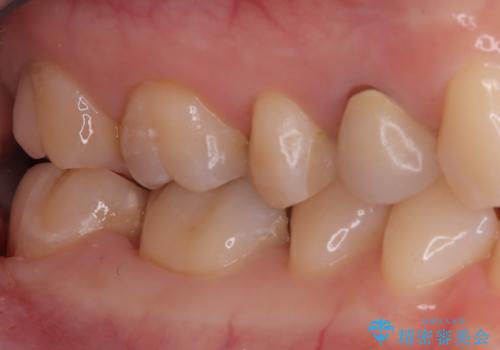

奥歯の銀歯を自然に!右下6番のメタルフリー治療

- 右下6番の奥歯に入っている金属の詰め物(メタルインレー)を気にされてご来院されました。お口の中の金属をなくしたいという患者様のご希望と、見た目の改善を目指し、天然歯に近い色と質感を持つセラミックインレーに交換する治療計画を立案しました。これにより、審美性の向上と、金属アレルギーのリスクがないメタルフリーの環境を実現することを目指しました。

治療では、まず古い金属のインレーを慎重に取り外し、内部に虫歯の再発がないかを丁寧に確認しました。歯を最小限だけ形成した後、精密な型取りから患者様の歯の色に合わせたオーダーメイドのセラミックインレーを作製しました。セラミックは、歯質との適合性が高く、プラークが付着しにくいため、虫歯の再発リスクを抑えるメリットもあります。適合性の高いセラミックインレーを装着することで、長年のコンプレックスだった銀歯がなくなり、機能的にも安定した自然な奥歯を取り戻していただけました。